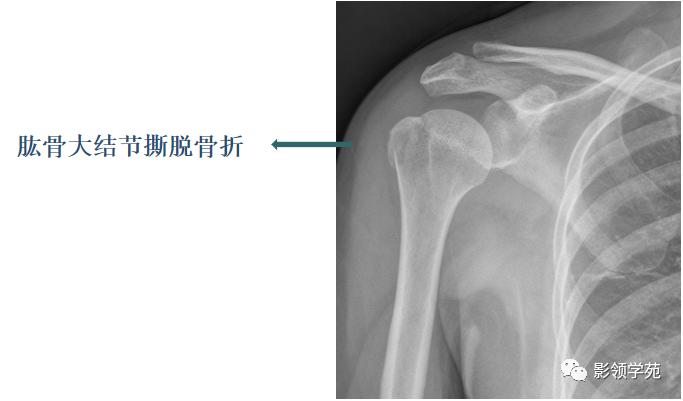

具有典型的好发部位,如肱二头肌肌腱附着处撕脱引起的肱骨大结节撕脱骨折。

具有骨折的直接、间接征象,例如撕脱后的游离骨及所对应的受损骨,其骨皮质不连续或缺损,且其边缘锐利、清晰(CT更能清楚显示);MRI可示局部软组织肿胀、积液或积血等改变;最有利的证据是伤后一段时间,上述征象发生了如边缘骨质吸收、有骨硬化、骨痂生长、局部软组织肿胀消退等动态改变。